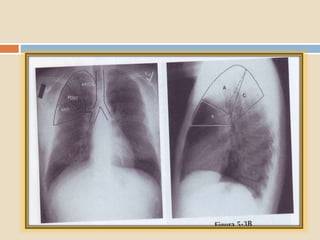

 El bronquio del LSD se origina próximo a la

carina. Se divide en tres bronquios

segmentarios: apical, anterior y posterior.

 El segmento lateral

está limitado por la

cisura menor en su

parte superior, tanto en

la placa PA como la

lateral.

 El segmento medial

está situado junto al

borde cardíaco derecho

, en su parte medial, y

contra la cisura mayor

en su parte posterior.

LATERAL

MEDIAL